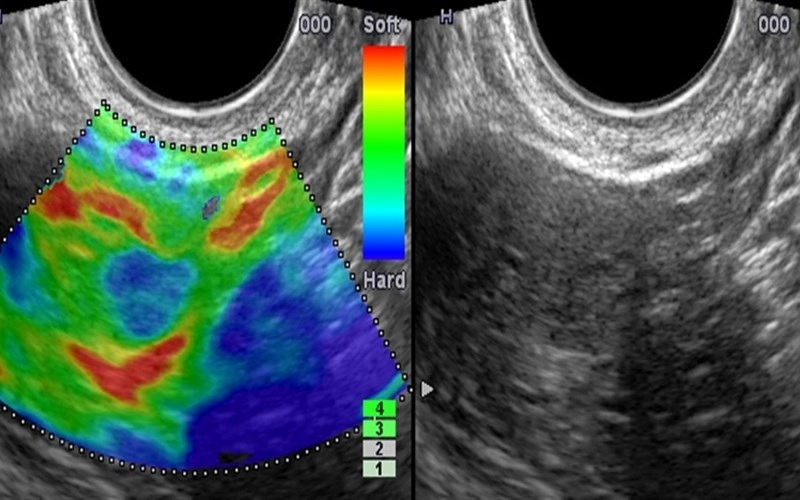

СоноэластографияСоноэластография – это медицинское обследование, при котором врач выявляет плотность мягких тканей. Процедура проводится с помощью ультразвука, она совершенно неинвазивна и безболезненна. Соноэластографию всегда проводят в комплексе с ультразвуковой ангиографией (обычным УЗ-обследованием). Эта процедура дополняет и расширяет информативность основного обследования. При УЗИ на экране появляется монохромное изображение внутренних органов. УЗ-эластография же выводит цветное изображение, где по тону цвета врач определяет плотность участка мягких тканей.

Эластография проводится вместе с УЗИ. На кожу пациента наносят специальный гель, который нужен для облегчения движения датчика. Врач водит датчиком по изучаемому органу, и на экране отображается цветовая карта мягких тканей. По этой карте врач легко определяет наличие уплотнений или других подозрительных элементов. Соноэластография позволяет получить результаты обследования сразу.